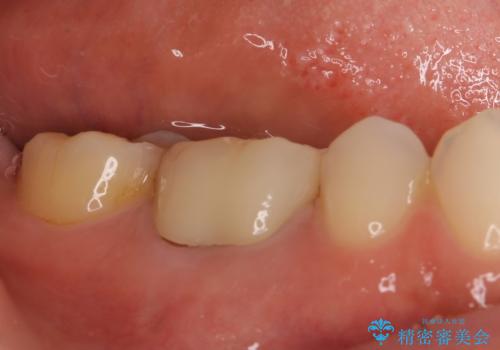

フルジルコニアクラウンを装着してからは、気になっていた金属の縁がなくなり、また、咬み合わせも非常に安定しており、患者様には大変満足していただきました。